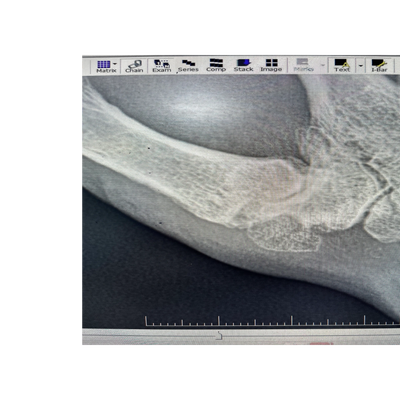

Thumb base arthritis xray

Thumb basal arthritis, also known as carpometacarpal (CMC) joint arthritis, is a common

degenerative condition affecting the base of the thumb. It is particularly prevalent in middle-aged and older adults, especially women. The CMC joint allows for the thumb’s wide range of motion, but this mobility also makes it susceptible to wear and tear arthritis and when this happens surgical options might be appropriate when conservative treatments such as splinting, medications, and injections fail to provide relief. This document explores

the main surgical options for thumb basal arthritis, including trapeziectomy and suspensionplasty, neurectomy, fusion (arthrodesis), and joint replacement (arthroplasty).